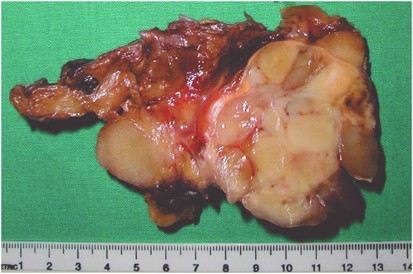

Gross features

The tumors ranged in size from 6 to 30 cm in greatest dimension (median=15 cm). Exact measurements were not available for the inoperable tumor (case 16), which was described as ‘large’ and occupying the entire posterior mediastinal cavity. Most of the tumors grossly resembled fat, and were multilobulated, well-circumscribed, and with a smooth outer surface covered by a thin fibrous capsule. In eight cases, the tumors showed a myxoid cut surface with focal gelatinous areas. Scattered solid areas were focally seen, particularly in the de-differentiated liposarcoma cases (Figure 1), and foci of necrosis and hemorrhage were also present in the myxoid/round cell and pleomorphic liposarcoma cases.